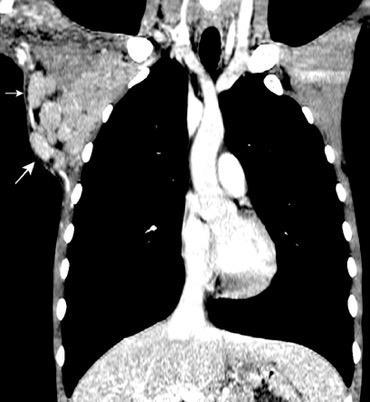

Masa axilar izquierda y derrame pleural derecho. Implantes pleurales, paraespinales . Ganglios en mamaria interna. Linfoma B difuso

Jaffe ES. Diagnosis and Classification of Lymphoma: Impact of Technical Advances.

2005. Masa pulmonar.

Linfoma NH de cél. B. Invasión Transtorácica.

Afectación axilar